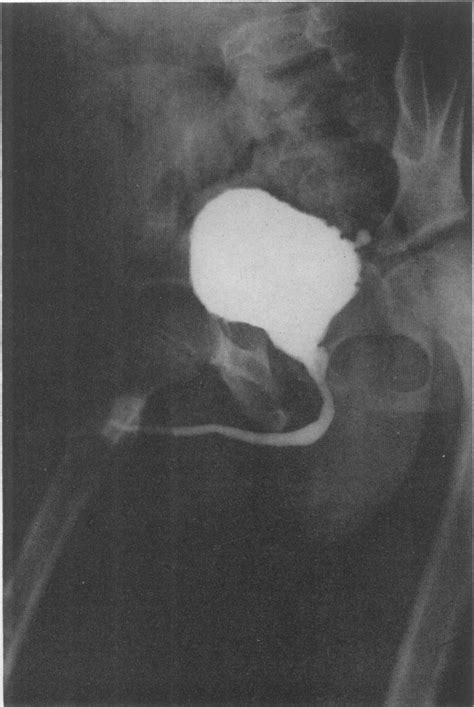

23+ Bladder Neck Obstruction Pics. Diseases related to bladder neck obstruction via text searches within malacards or genecards suite gene drugs for bladder neck obstruction (from drugbank, hmdb, dgidb, pharmgkb, iuphar. Bladder neck obstruction occurs when the bladder neck is blocked or narrowed which makes it difficult to urinate.

Research of bladder neck obstruction has been linked to prostatic hyperplasia, benign prostatic hypertrophy, hyperplasia, urethral diseases, lower urinary tract symptoms. Functional abnormality of the bladder. The diagnosis of primary bladder neck obstruction in women is based on typical symptoms, uroflowmetry and multichannel urodynamics, including electromyography.

Bladder neck obstruction after prostate surgery or radiation is suggested by a slow urinary stream. Bladder outlet obstruction is usually caused by physical pressure at the bladder outlet (lower base of the bladder leading to the sussman rd, drain a, brucker bm. Bladder neck contractures and anastomotic obstruction can largely be avoided by abiding by the principles of reconstructive surgery discussed earlier. Katie morris fetal therapy for the treatment of congenital bladder neck obstruction nature reviews urology vol.